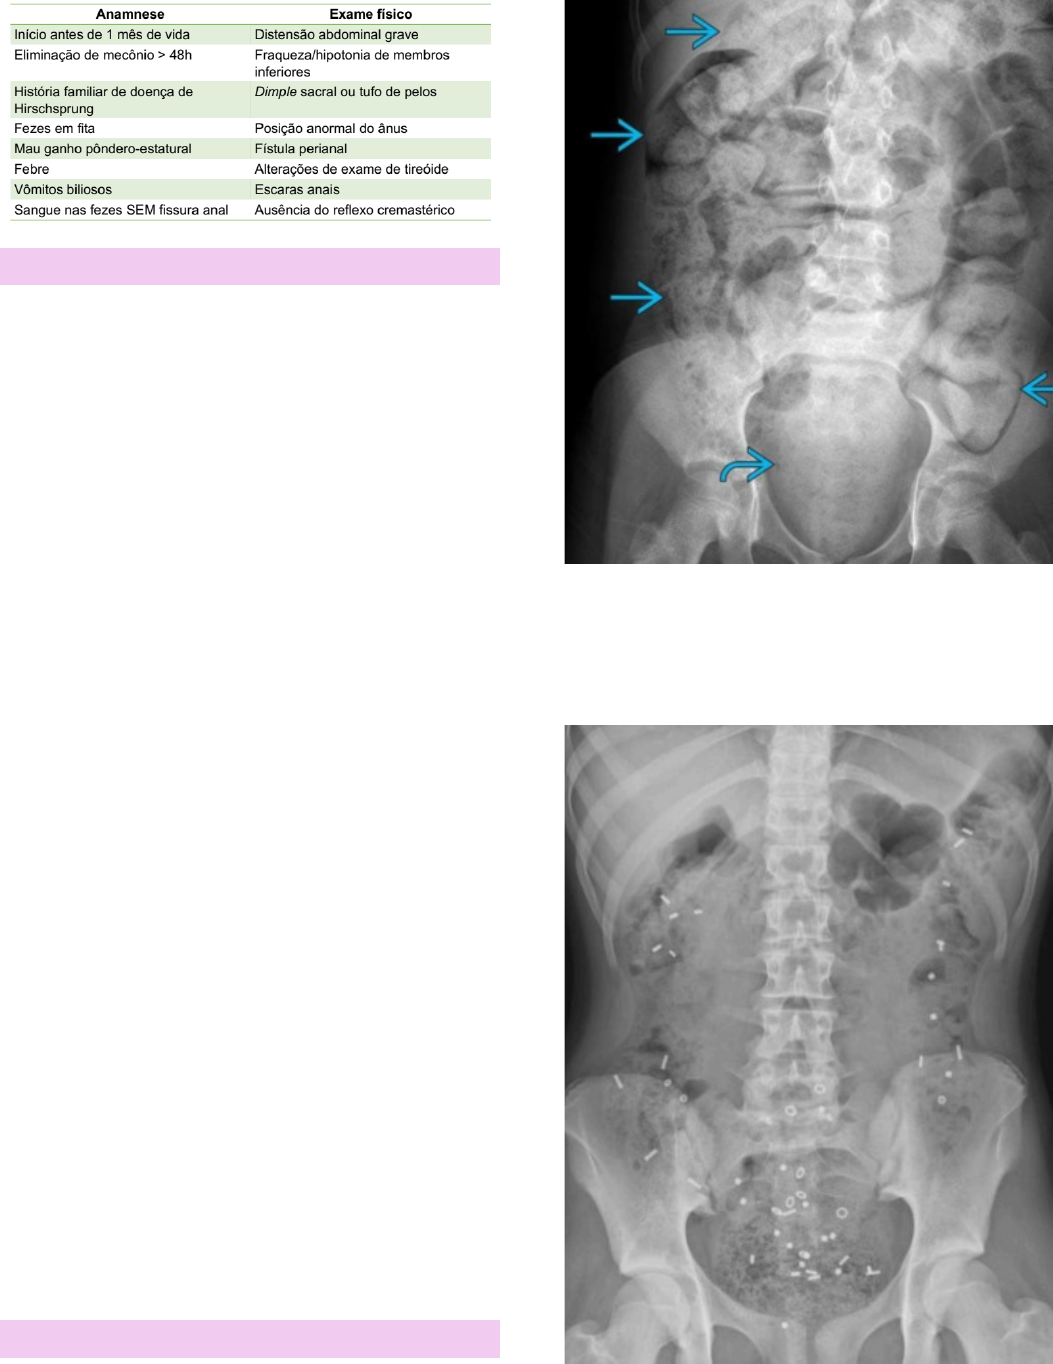

Obstipação em Idade Pediátrica | Concise Medical Knowledge

image size: 810x1080